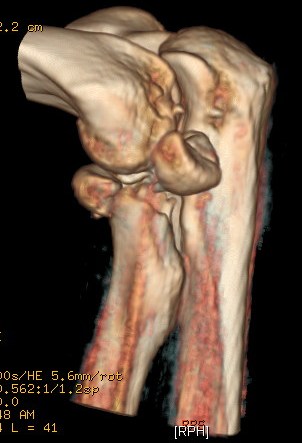

En los quince años que llevamos trabajando en este ámbito asistencial era la primera vez que veíamos un caso así. Esto tiene sus ventajas e inconvenientes. Entre las primeras que suspone una oportunidad de aprendizaje personal o compartido. Entre las segundas la incertidumbre ante la probable evolución y el resultado funcional para el paciente. Expondremos ahora cuáles han sido estos. Contamos, además, con una potente herramienta diagnóstica que facilita el trabajo del médico traumatólogo a la hora de la intervención. Se trata de la tomografía con la que se hace una reconstrucción tridimensional de la estructura estudiada. Podemos ver la fractura con un fragmento volteado hacia posterior: